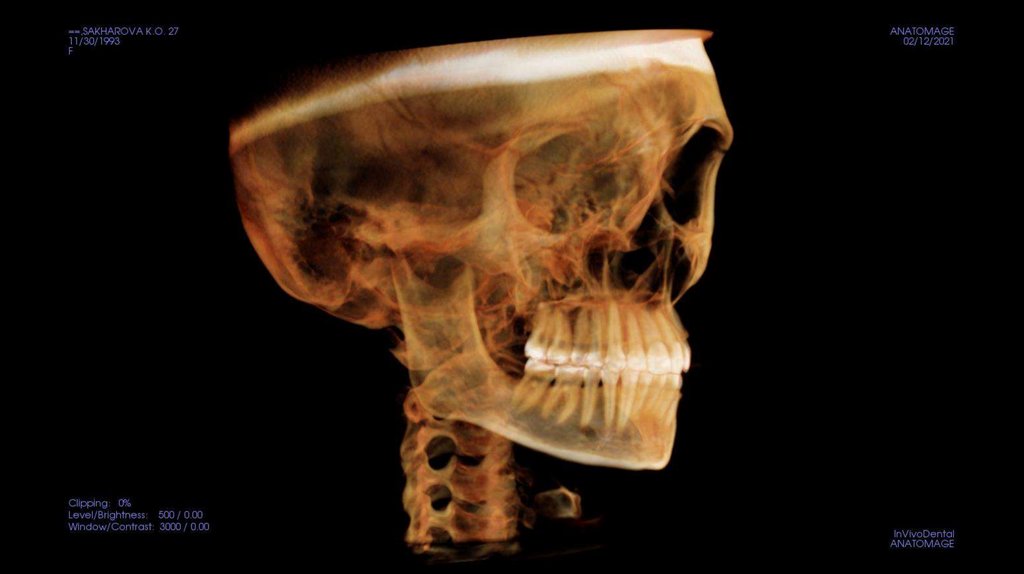

По рассчетам снимков:

• Ретрузия резцов верхней челюсти

• Компрессия головок суставов, особенно правого( началось

ремоделирование)

• Костная ассиметрия(10 мм)

• 2 класс

• 25, 46 зуб – нуждается в санации

• Требуется профессиональняа гигиена полости рта

• Клиновидные дефекты 43, 44

• 18, 28, 38, 48 отсутствуют.